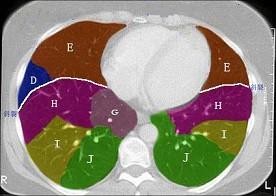

问题 结合肺段模式肺动脉干与右肺动脉层面(见图), 心室层面(见图), 主动脉弓层面(见图), 左右心房层面图(见图),选出左肺下叶的组成 ( )

选项 A、D+E+F+G+H+I+J B、C+D+E+F+G+H+I+J C、F +H+I+J D、E+F+G+H+I+J E、G+H+I+J

答案 C